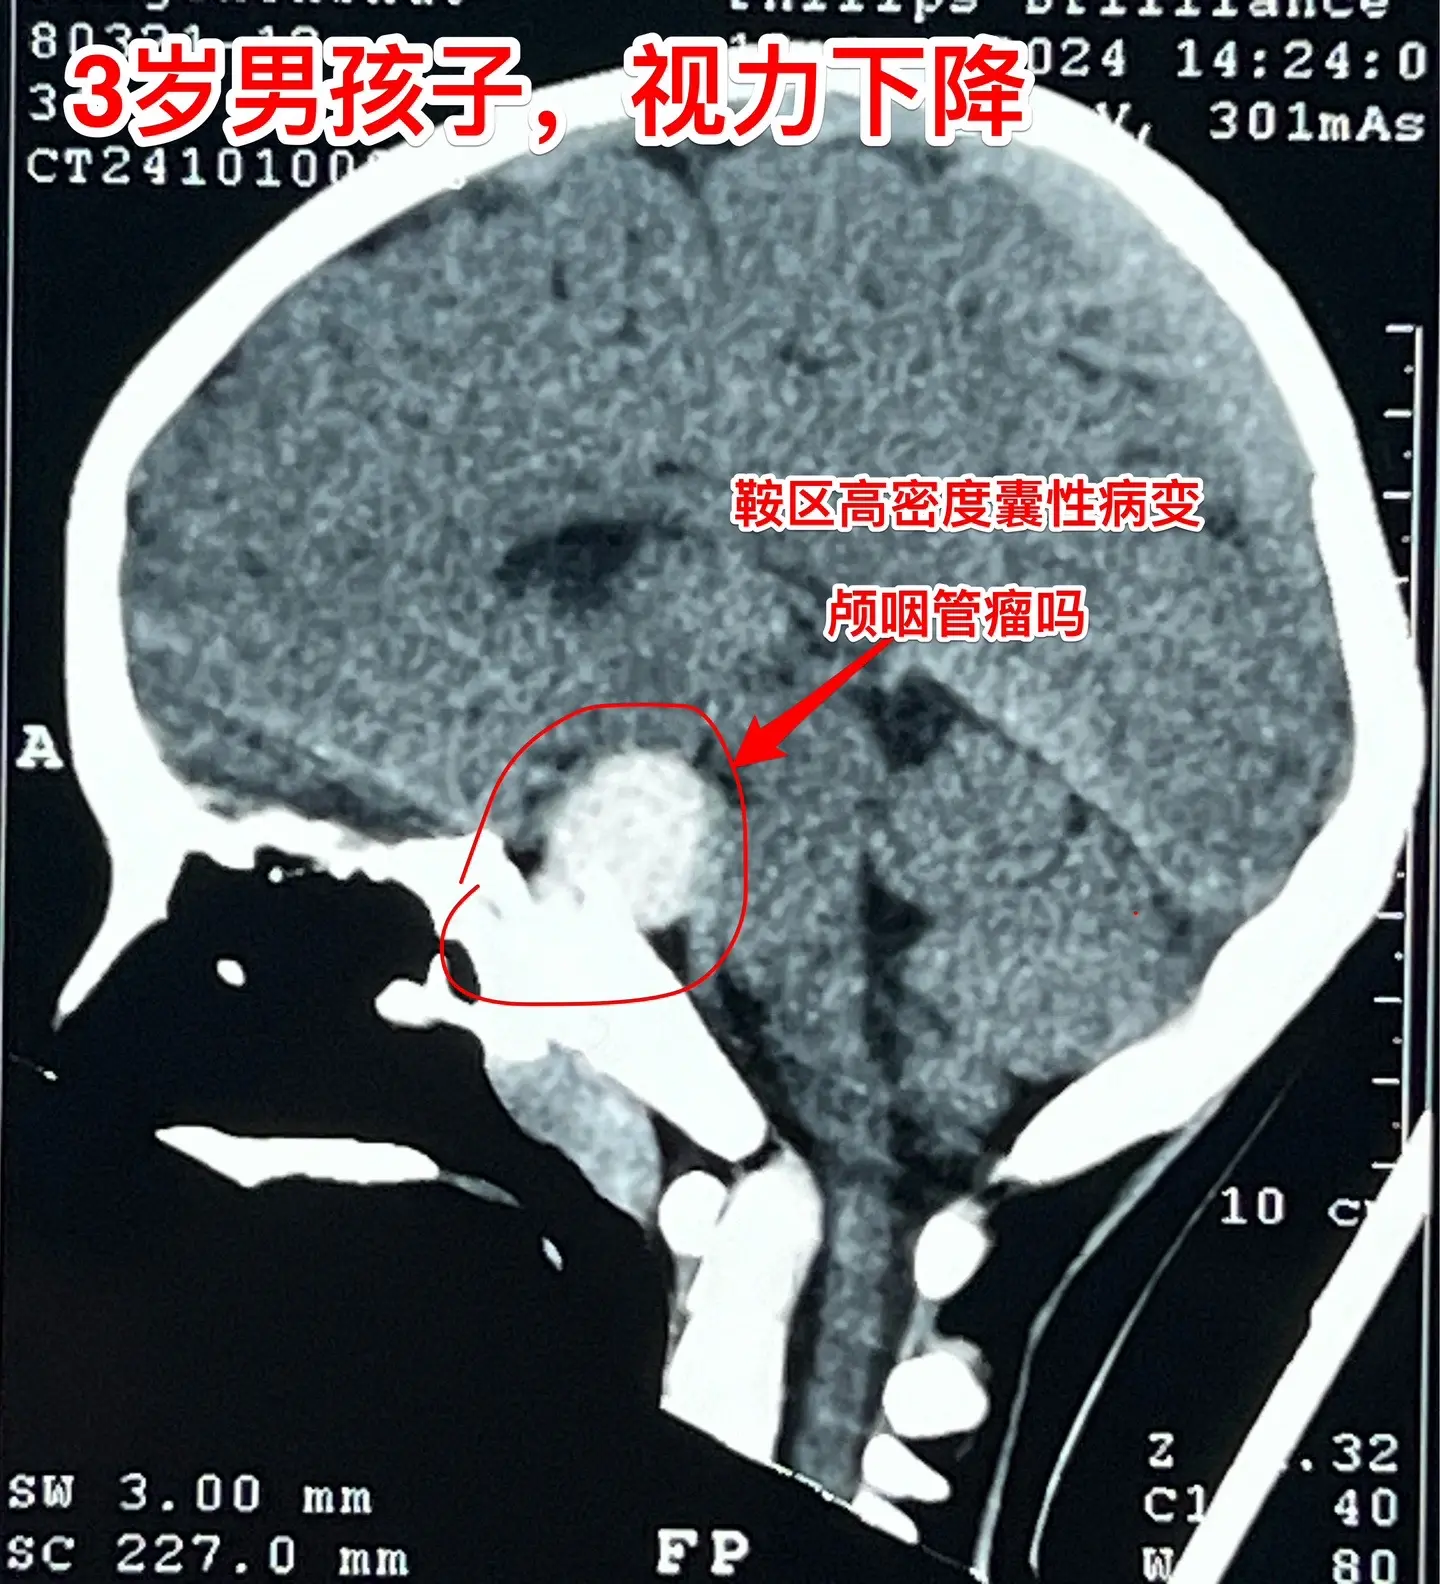

鞍区高密度囊肿-高密度不等于钙化。拉克氏囊肿在CT扫描中大多数呈低密度影,少数呈现比较均匀的高密度影,但是绝对不是钙化。不能误认为是颅咽管瘤。 三岁男孩子因偶然原因行CT扫描发现鞍区病变。测视力才发现患儿的视力有下降(0.3)。根据CT、磁共振可以判断这是拉克氏囊肿,病变没有钙化。 拉克氏囊肿如果压迫视神经、视交叉造成视力下降或者视野缺损,则有手术指征。 今日10.25经翼点入路将病变切除。术中快速冰冻报告为拉克氏囊肿。